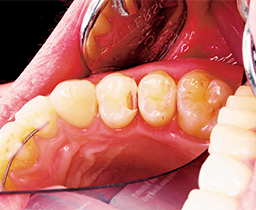

A topical anesthetic was placed on the papila. A fender wedge was placed preoperatively to protect the adjacent tooth (Fig. 2).

Fig. 2 Fig. 3

The contact was broken bucco-lingually and gingivally with the fender wedge in place (Fig. 3). The fender wedge was removed in order to evaluate the prep (Fig. 4).